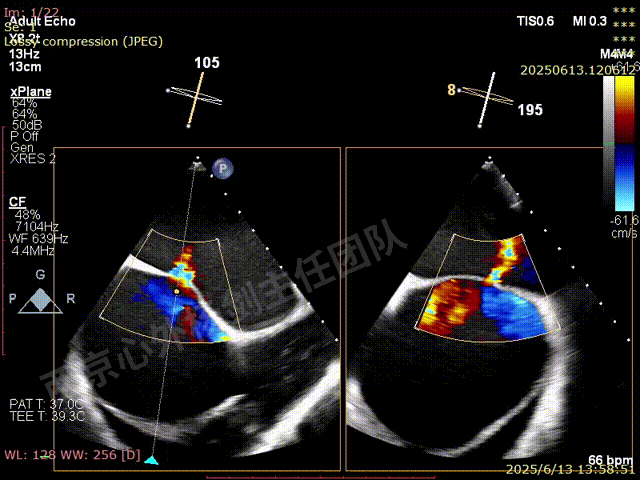

二尖瓣后叶栓系严重,前叶相对错位,反流束沿2区分布广泛,2偏3区处存在反流。

反流宽度至少23mm,因影像调整困难,考虑实际反流更宽。